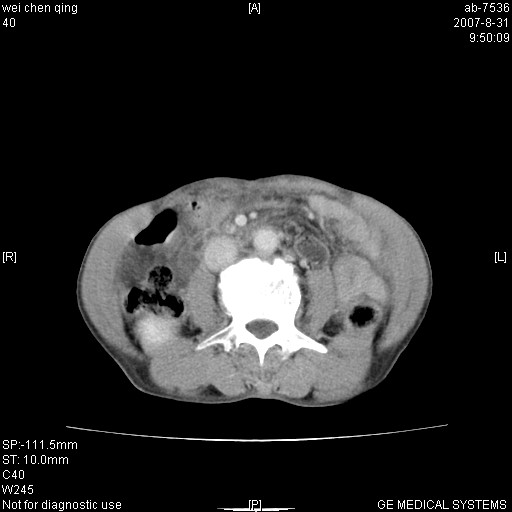

以下是引用zyyzzy在2007-8-31 14:34:00的发言:[br]该病人肝内胆管扩张,胆囊及胆总管未见明显扩张。在倒数第9层图像上可看到左右肝管结合部(肝总管)有软组织影,此处应薄层扫描。考虑肝总管占位(ca)、腹水。[br]